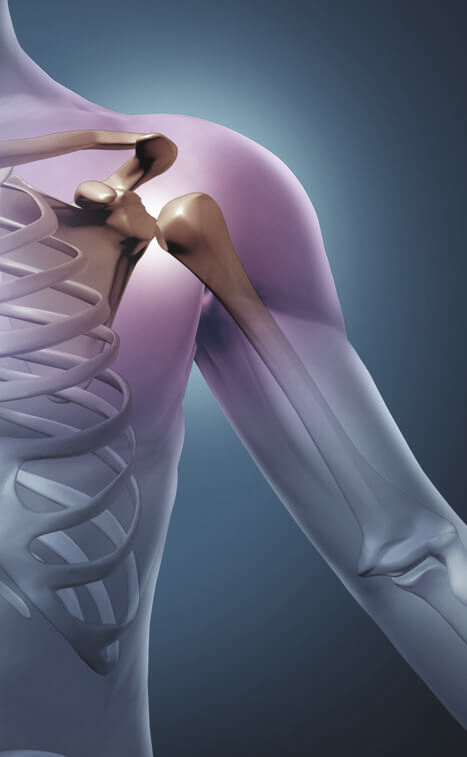

Go to the Rotator Cuff Pain Workshop and Learn:

The Single Worst Position to Sleep in That Causes BIG Problems in the Shoulder and Rotator Cuff...

The #1 Biggest Mistake People Suffering with Shoulder Pain Make Which Surprisingly Can Lead to Rotator Cuff Surgery...

The Common Causes of Rotator Cuff Problems...